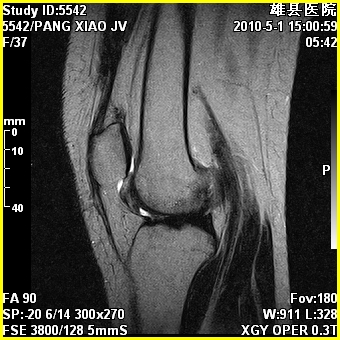

标题: MRI2894:患者右膝关节疼痛两月余,无明显外伤史 [打印本页]

标题: MRI2894:患者右膝关节疼痛两月余,无明显外伤史

右股骨下端前内侧类圆形异常信号,位于干骺端,呈长t1长t2改变,但信号不均,t1图上病灶中心见小片状稍高信号影,t2图上见散在稍低信号影,stir像呈高信号,因病灶较小,缺乏特征性改变,结合患者年龄及部位,考虑嗜酸性肉芽肿可能性大。胫骨关节面下的小囊状异常信号,如果一元论考虑则为嗜酸性肉芽肿,不过发生在这个部位的少见,二元论考虑为邻关节骨囊肿。半月板与前后交叉韧带均未见异常。

右股骨下端前内侧干骺端囊性良性病变,考虑 1内生软骨瘤 2骨囊肿 3肉芽肿。